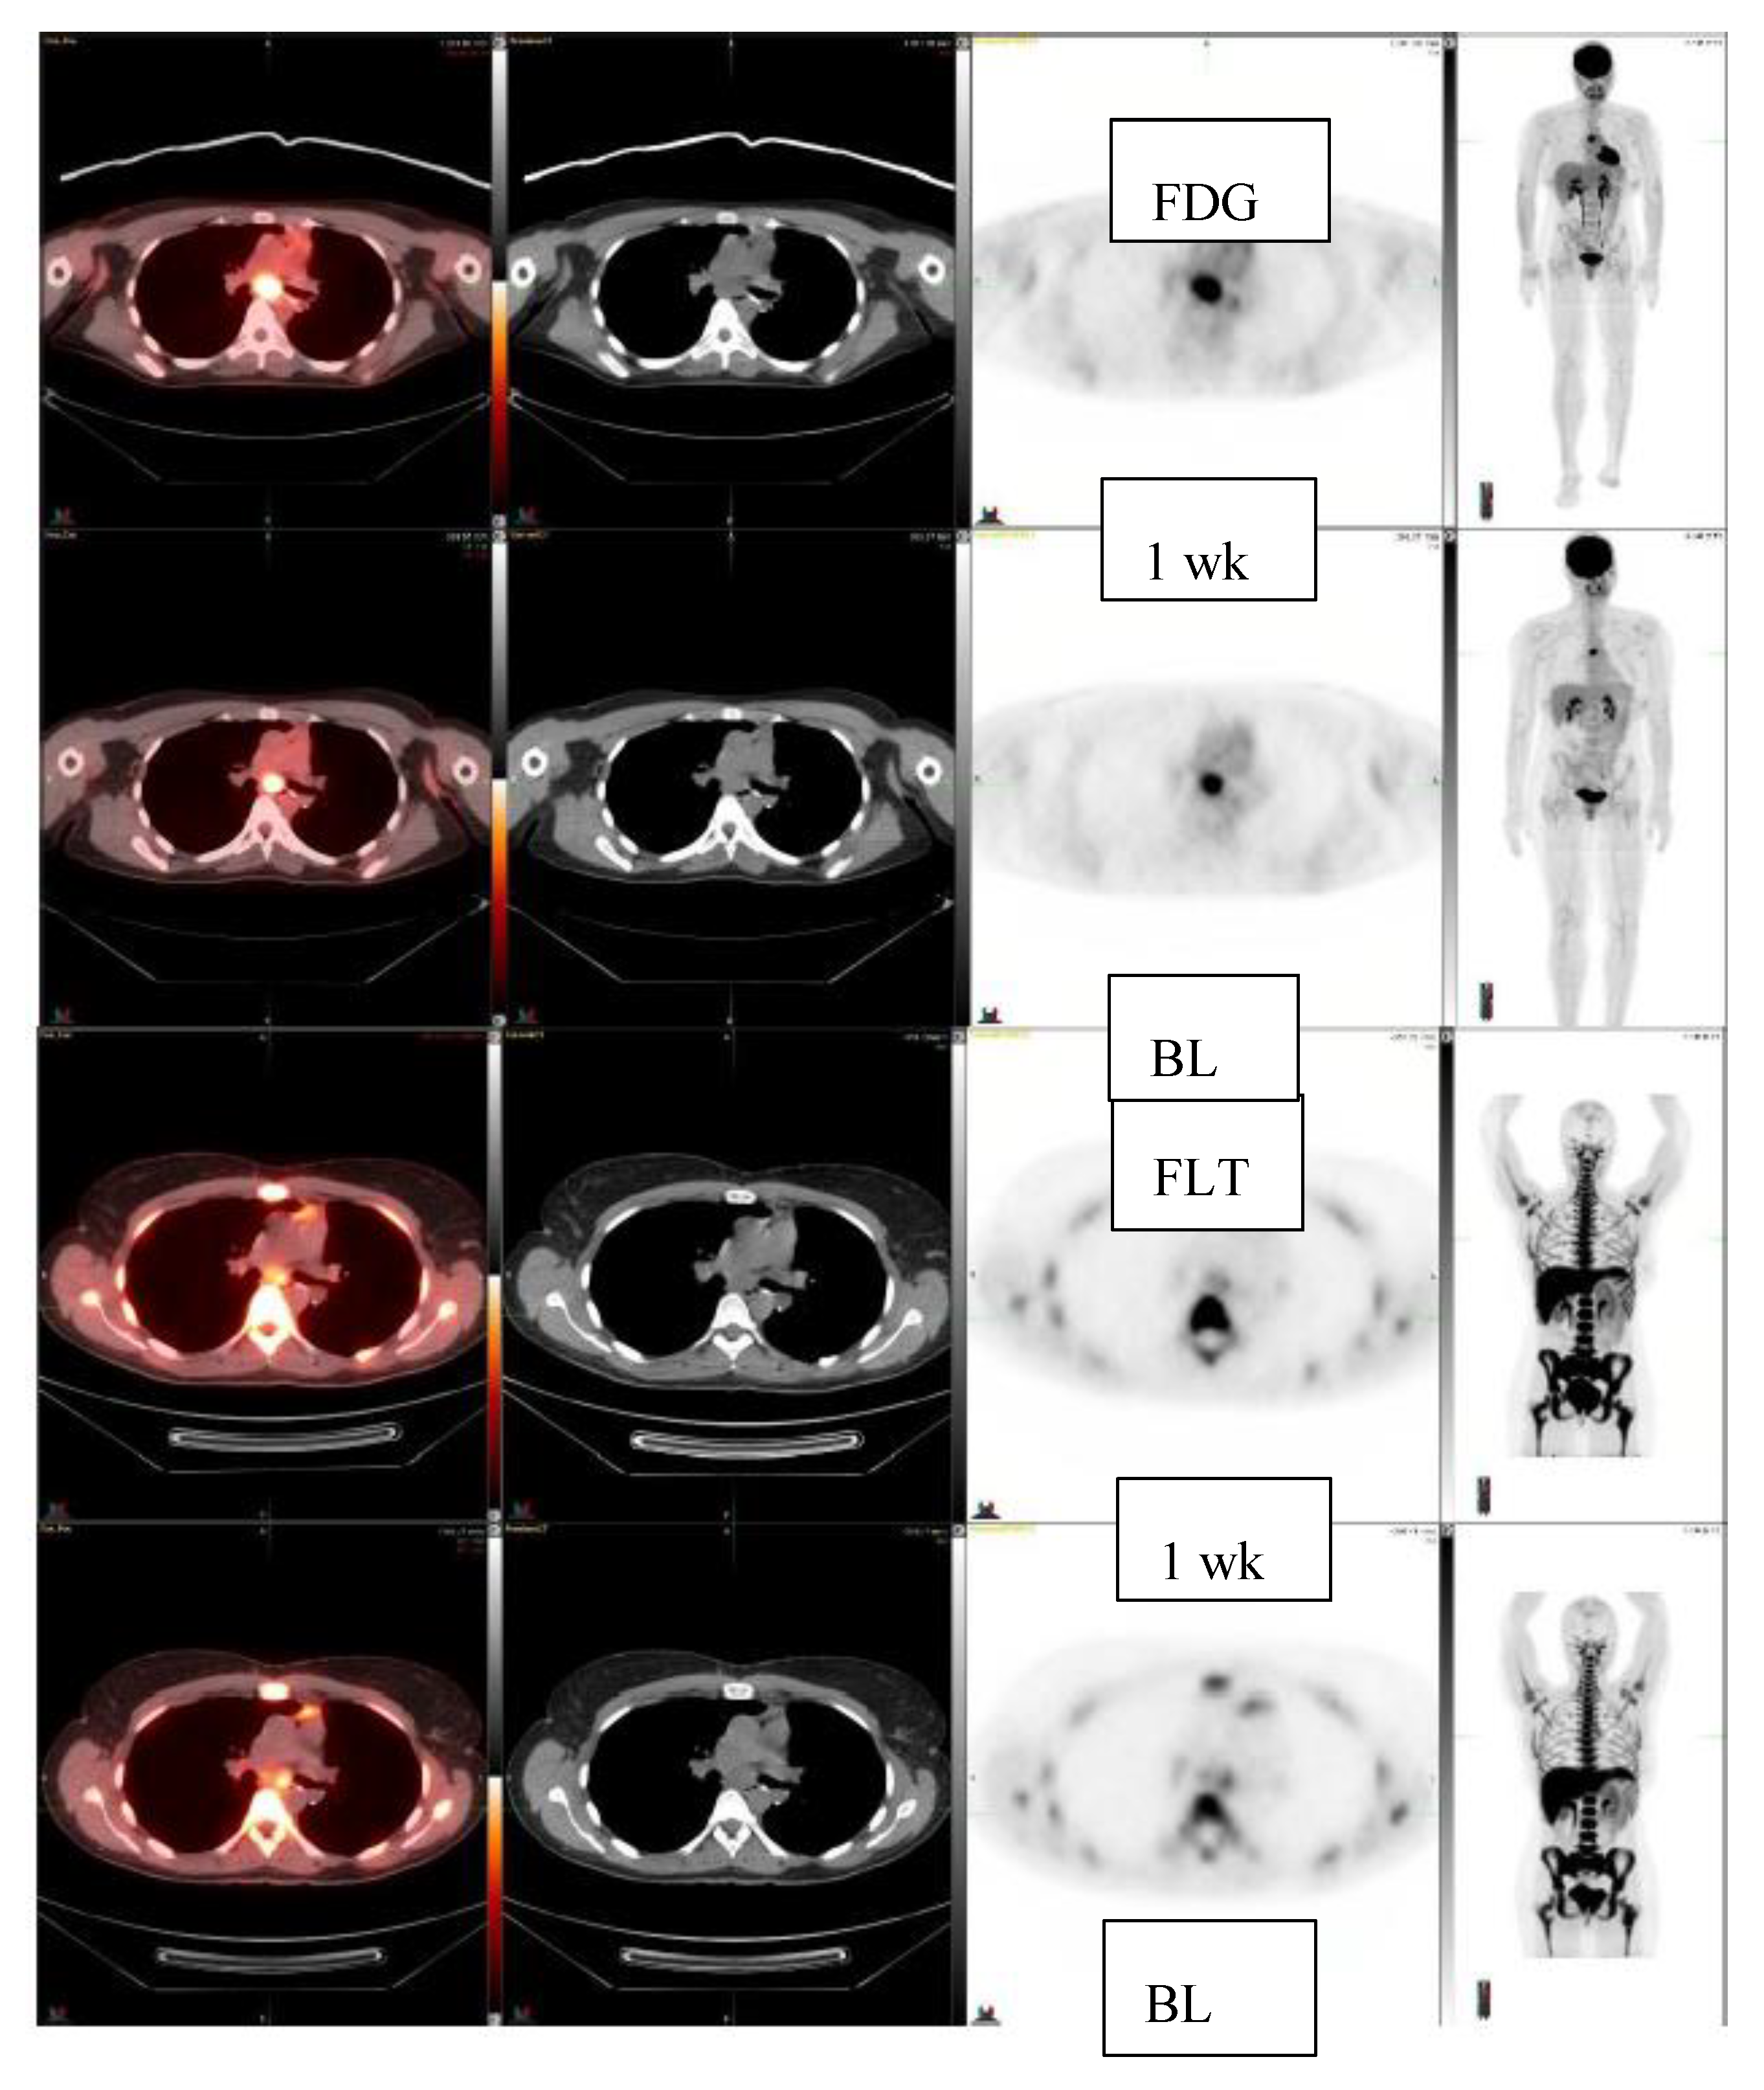

Figure 3.

Clear cell sarcoma, left foot, lung resection. FDG-study at baseline and at 1 week (2 upper rows). FLT-study at baseline and at 1 week (2 lower rows). FDG-uptake increases 37% in a subcarinal lymph node: SUVmax 8.9 ->12.2, whereas FLT-uptake decreases 13%, FLT: SUVmax 3.0 ->2.6. On CT it becomes slightly bigger, CT: 2.2 cm × 1.2 cm ->2.3cm × 1.5 cm.

Next, 10 patients who were treated with c-met inhibitor (5 patients) or -2 inhibitor (5 patients) and had a total of 11 lesions were studied for early response with FLT (Table 2). They were studied at baseline and once after the initiation of the new therapy at 1–4 weeks. Five patients demonstrated FLT response, three patients had no change, and two patients progressed. Among these patients, two anecdotal patient cases are detailed in the figures. A patient with clear cell sarcoma of the left foot was studied at baseline and at one week with 18F-FLT and with 18F-FDG (Figure 3). This patient had a sub-carinal lymph node metastasis. With 18F-FLT, the outcome at one week was −13% (R), whereas 18F-FDG did not show any response +37%, and SUVmax increased from 8.9 to 12.2. On CT scans, the tumor was slightly larger: 2.2 cm × 1.2 cm →2.3 cm × 1.5 cm (Figure 3). In Figure 4, a patient with a fibrous tumor in pleura is shown, demonstrating a right lung mass. The patient was studied at baseline and at 1 week with 18F-FLT and the concentration decreased −43%. On CT, the tumor was slightly larger: 2.4 cm × 1.9 cm →2.5 cm × 2.0 cm (Figure 4).

Here, we have shown that multiple sarcoma subtypes can be imaged using FLT (Figure 1, Figure 2, Figure 3 and Figure 4. Figure 1 demonstrates that FDG uptake increases early, whereas FLT remains stable or decreases. The FDG uptake may also demonstrate pseudoprogression, which is typical for immunotherapies. Similarly, in Figure 3, the FLT uptake decreases and FDG uptake increases. We also see that the decrease in cell proliferation can be imaged using FLT in spite of the SUV level (Figure 1, Figure 2, Figure 3 and Figure 4).